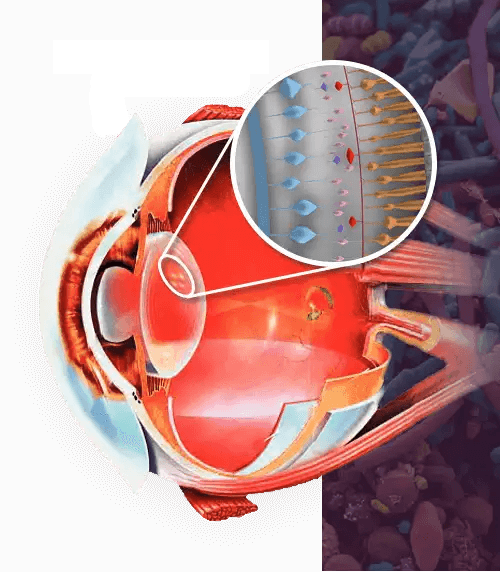

Vizinex es un complejo nutritivo de extractos naturales que tienen un efecto direccional en caso de reducción de la visión y combaten por completo las enfermedades más comunes del ojo humano.

- Luteína: protege la retina

- Arándanos: ayudan a reconstruir la retina

- Zeaxantina: ayuda a mantener los músculos de los ojos saludables y a reducir la fatiga

- Vitaminas: mejoran la claridad de los ojos

- Minerales: fortalecen los capilares y las venas de los ojos

Son las únicas gotas orales que regulan la función de los músculos del globo ocular, ayudando a restablecer el enfoque y a recuperar una visión clara, brillante y tridimensional.

Fortalecen los músculos visuales

Los componentes de Vizinex aumentan el tono del músculo ciliar que soporta el cristalino y evitan que se tense demasiado

Mejoran el suministro de sangre a los ojos

Estas gotas aumentan la elasticidad de las arterias oftálmicas y estimulan el flujo sanguíneo hacia la retina y la córnea

Aumentan la claridad y el brillo de la visión

Después de un ciclo de tratamiento con Vizinex, distinguirás mejor los colores, verás los contornos de los objetos con mayor claridad, leerás la letra pequeña y tus ojos no se cansarán del trabajo prolongado delante del ordenador